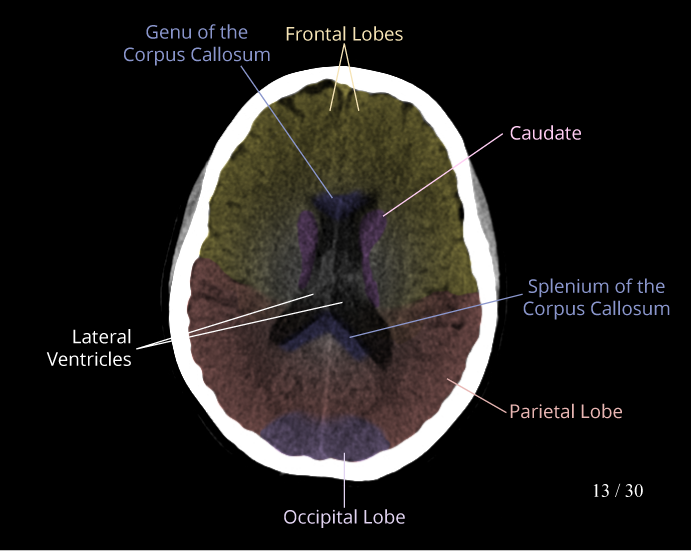

CT Brain Anatomy